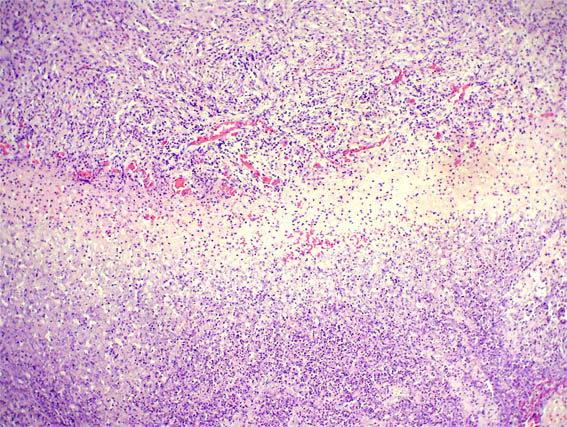

The patient is a 67-year-old woman with renal mass that completely replaced the left kidney. No lithiasis.

Nephrectomy was done.

Figure 1.